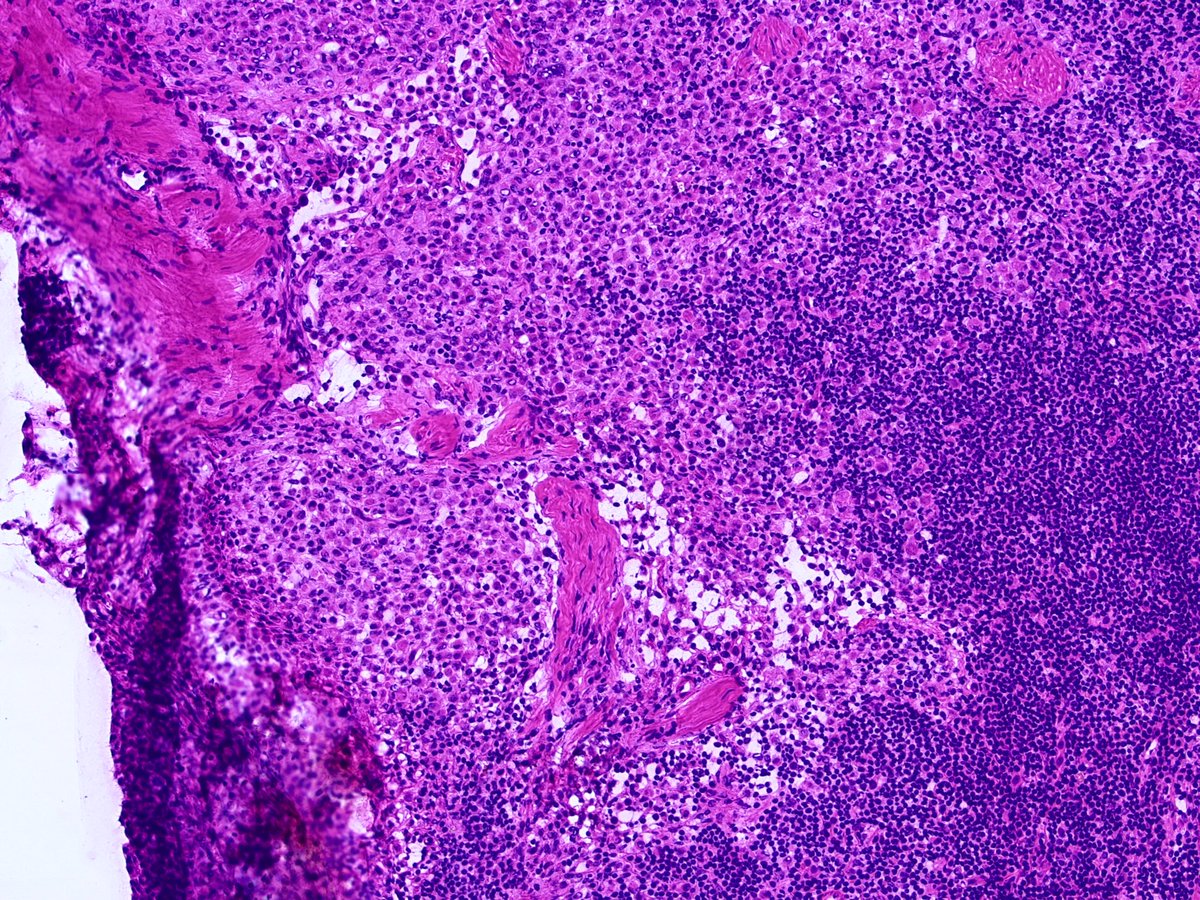

52 Year old female; multifocal right sided breast cancer undergoing mastectomy with SLN bx.

Intraoperative sentinel node touch prep shown. If cancer —> axillary dissection.

Diagnosis? Comments encouraged. Histology correlation and discussion to follow.

1. Discussion: Interesting voting trend. “Benign” held the early slight majority, then some astute people suggested metastatic lobular carcinoma. The voting them swung decidedly towards “cancer”!

None of these are specific; histiocytes may resemble lobular cancer cells. However, taken together, these atypical features should raise concern for malignancy, and prompt a frozen section.